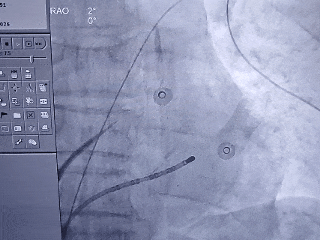

房间隔穿刺

射频消融前穿刺双孔

DSA造影复测缺损

右肩位:RAO 30° +CRAN 20°

肝位:RAO 30° +CAU 20°

术中肝位测量:

心耳开口直径:24.9mm

心耳深度:26.9mm